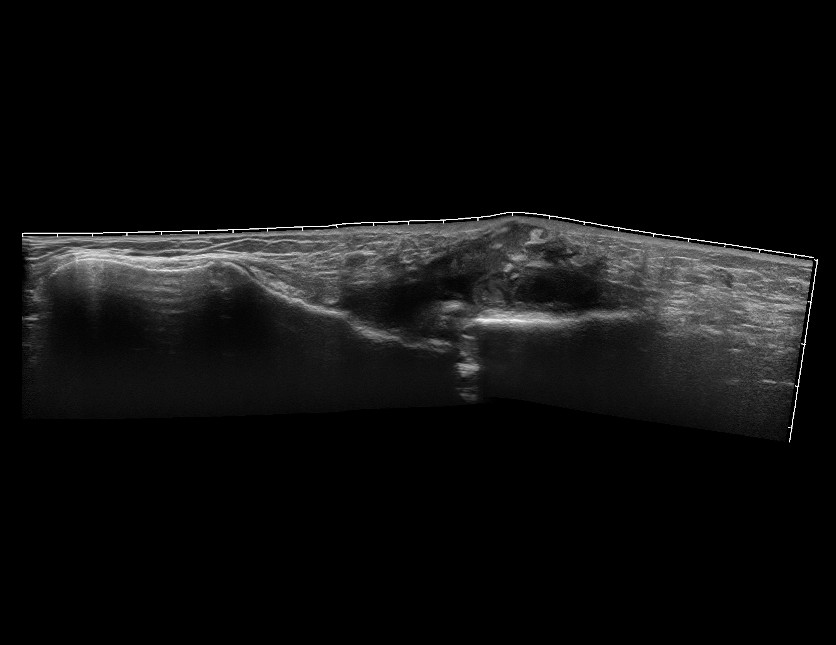

Перелом грудины, гнойное воспаление мягких тканей

Мужчина, перелом грудины.

20190326_131141_19.jpg